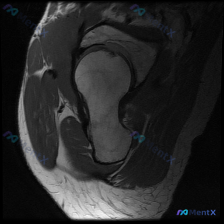

整理了一份肩部MRI病例讨论材料,医生的核心问题是排查盂唇病变,但看影像发现了一些矛盾点。先放MRI T2序列冠状位的分析: 1. 骨性结构:肱骨头、肩峰及锁骨远端轮廓尚可,未见骨折线或骨髓水肿 2. 肌腱与肩袖:冈上肌腱在肱骨大结节止点处形态异常,连续性中断,T2高信号 3. 关节与滑囊:肩峰下-...

最近整理了一份肩部MRI的病例讨论材料,患者主要问题是肩部疼痛,但问题明确指向"盂唇病变"范畴。先看T2冠状位图像的关键发现: 1. 冈上肌腱在肱骨大结节止点处有显著高信号,连续性可能中断 2. 肩峰下-三角肌下滑囊有明显的高信号积液 3. 关节盂唇区域信号存在改变 大家觉得这个病例更符合哪种诊断?...

整理了一个肩关节MRI-T2序列冠状位的病例讨论材料,医生提问关注盂唇病变,但影像最突出的是冈上肌腱全层撕裂。这份病例的核心疑问点和影像发现存在一定不匹配,大家第一眼怎么看?

看到一个肩部MRI(冠状位)的病例资料,用户最初的问题是关于「盂唇病理」,但整理的分析报告里有几个点挺值得讨论的: 先放影像的关键发现: - 冈上肌腱连续性中断,断端回缩,伴冈上肌肌腹萎缩、脂肪浸润 - 肩峰下-三角肌下滑囊积液,肩峰下间隙变窄,肱骨头上移 - 肱骨头大结节下方骨髓水肿 - 盂唇形态...